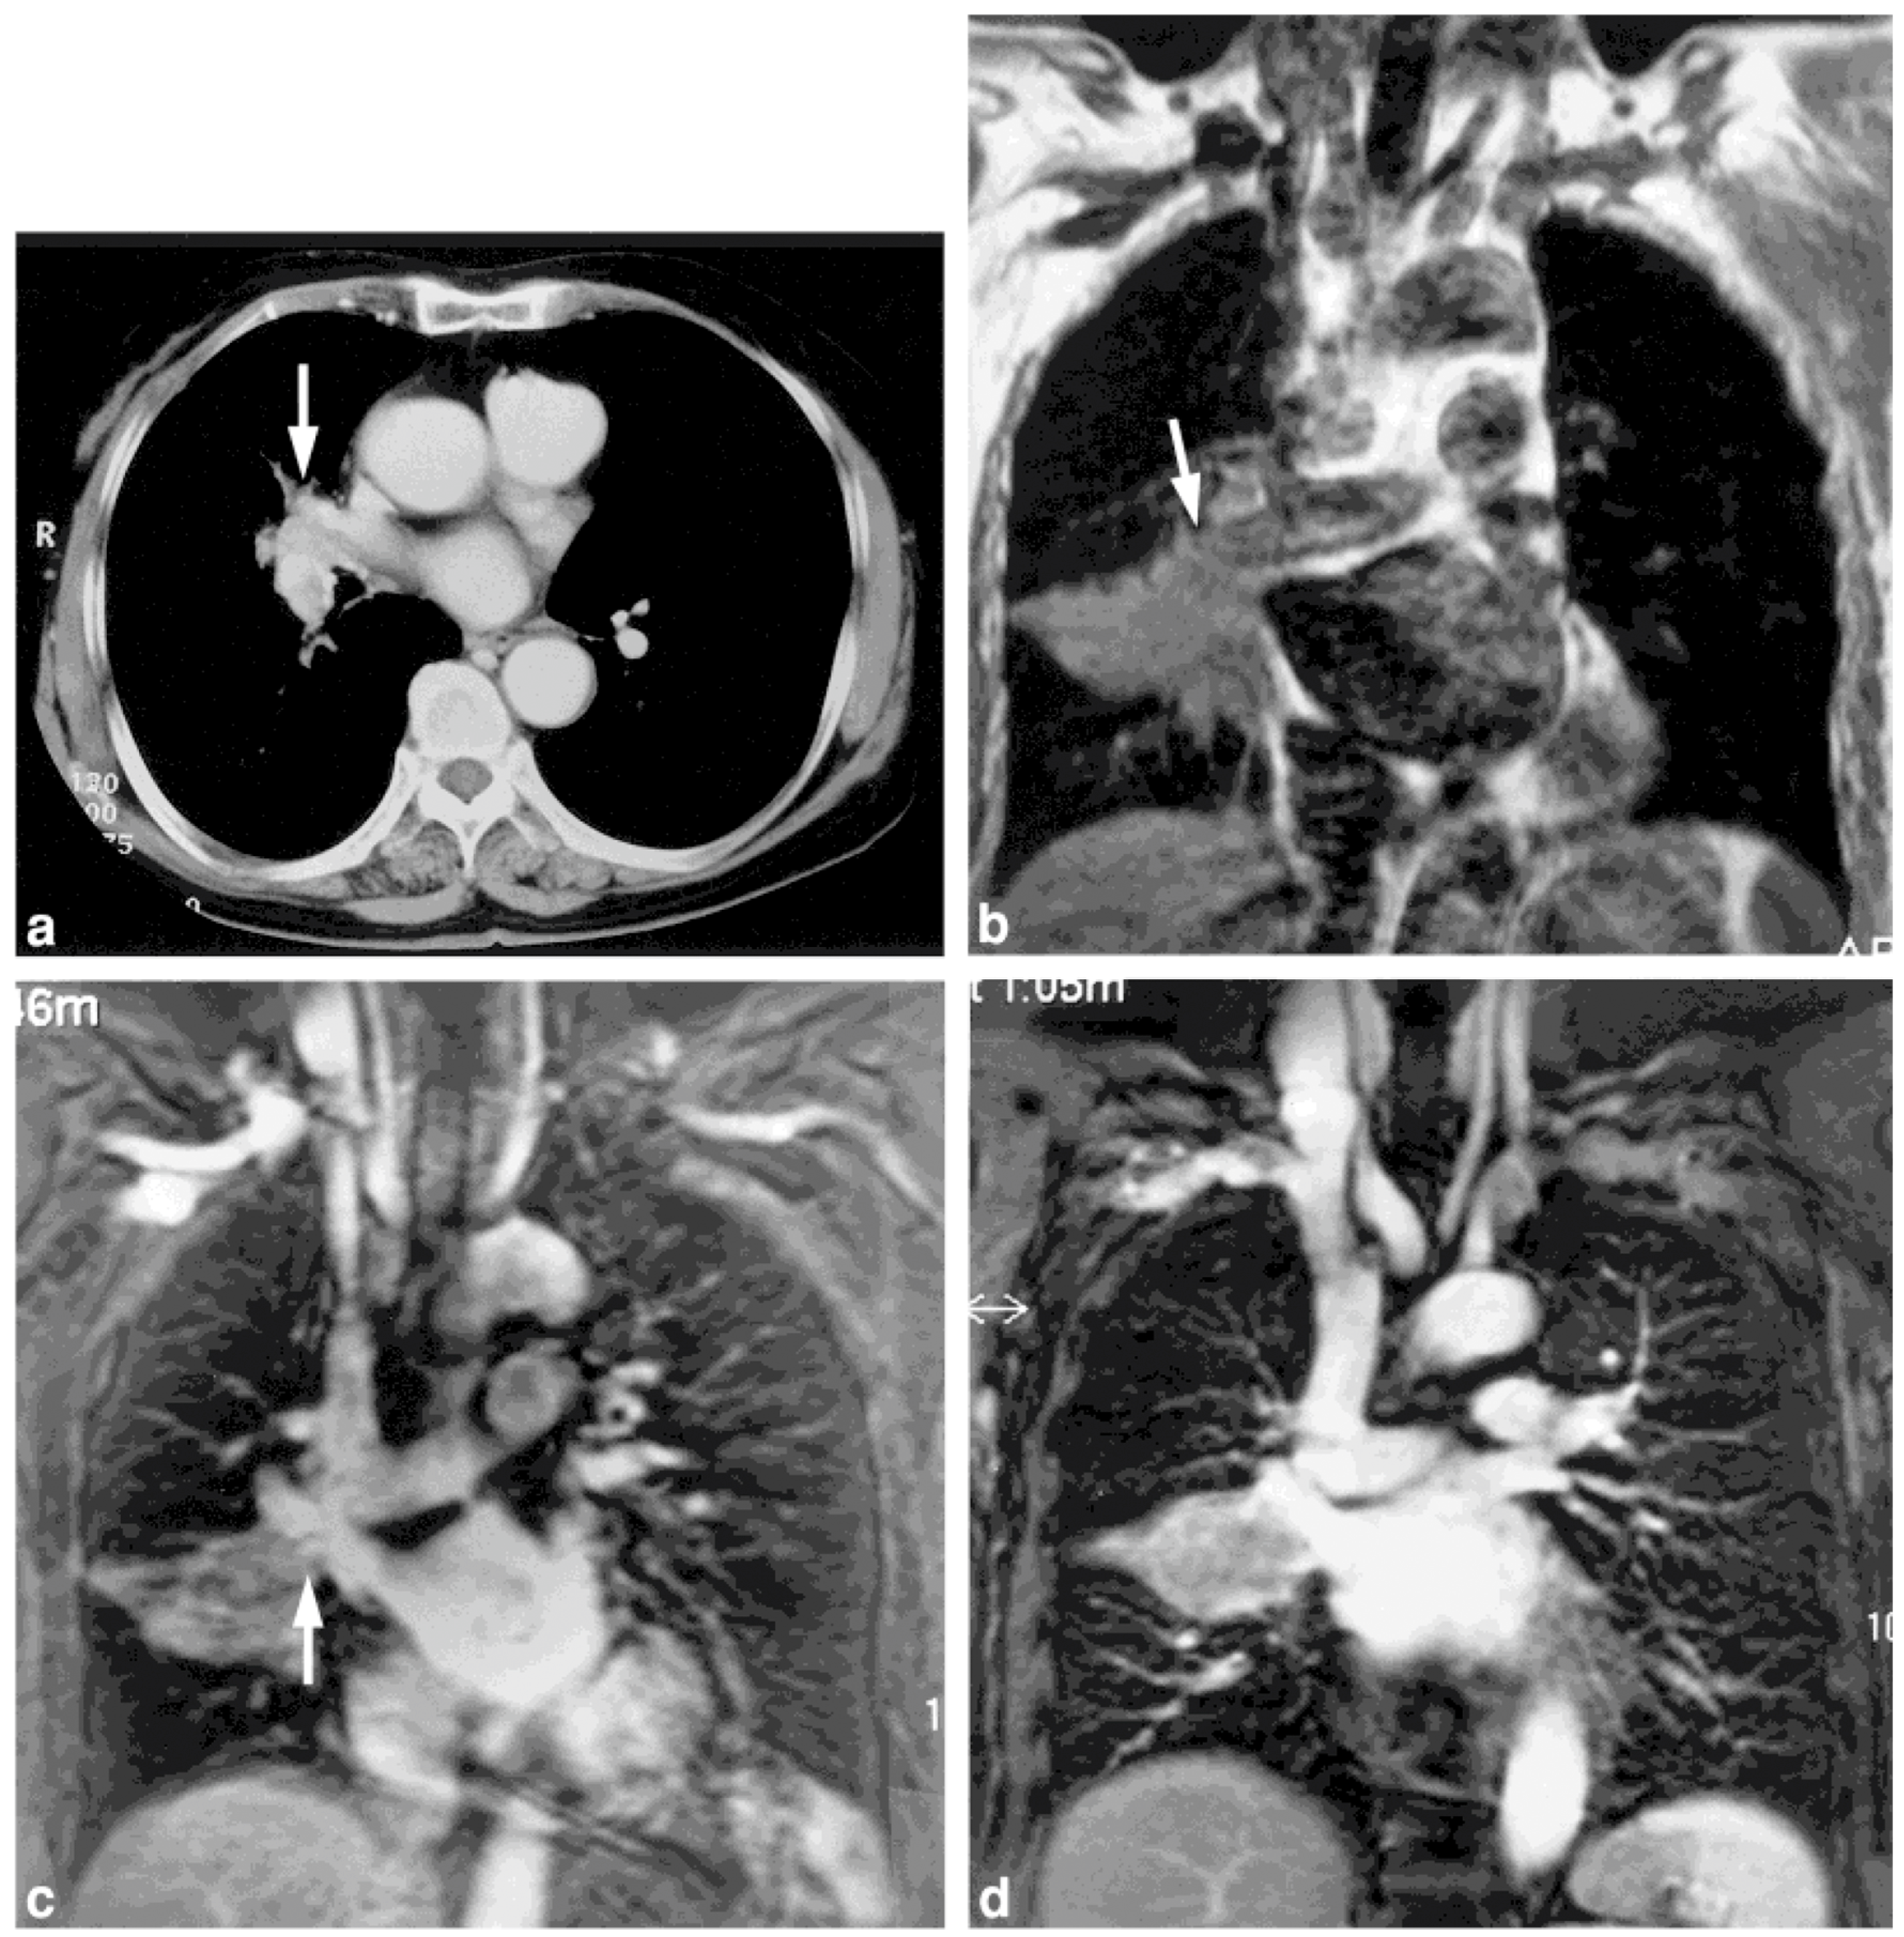

- Ohno, Y.; Adachi, S.; Motoyama, A.; Kusumoto, M.; Hatabu, H.; Sugimura, K.; Kono, M. Multiphase ECG-triggered 3D contrast-enhanced MR angiography: Utility for evaluation of hilar and mediastinal invasion of bronchogenic carcinoma. J. Magn. Reson. Imaging 2001, 13, 215–224. [Google Scholar] [CrossRef] [PubMed]

- Ohno, Y.; Nishio, M.; Koyama, H.; Yoshikawa, T.; Matsumoto, S.; Seki, S.; Sugimura, K. Journal Club: Comparison of assessment of preoperative pulmonary vasculature in patients with non-small cell lung cancer by non-contrast- and 4D contrast-enhanced 3-T MR angiography and contrast-enhanced 64-MDCT. AJR Am. J. Roentgenol. 2014, 202, 493–506. [Google Scholar] [CrossRef] [PubMed]

2.1. T-Factor Assessment